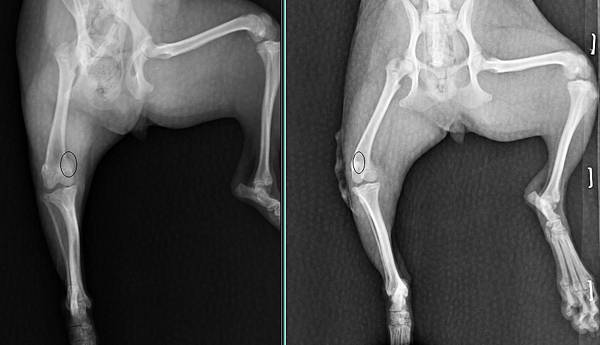

chubby在長大的過程中

膝蓋骨漸漸的脫就跑出來

於是安排手術修復

手術後目前恢復非常棒